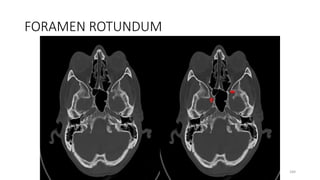

Foramen rotundum

Content

• Maxillary nerve (V2)